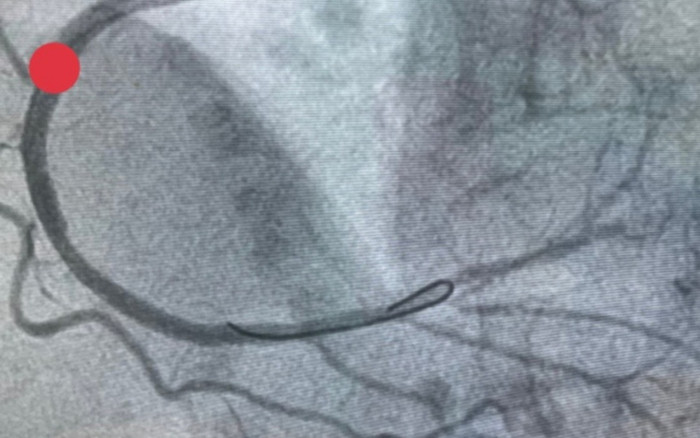

Hình ảnh chụp động mạch vành sau can thiệp đặt stent. (Ảnh: SKĐS).

Chụp động mạch vành qua da cấp cứu, kết quả tắc hoàn toàn động mạch vành phải, tắc mãn tính động mạch liên thất trước. Trước tình trạng nguy cấp, các bác sĩ tiến hành can thiệp đặt 2 stent động mạch vành phải nhằm tái thông động mạch cho người bệnh.

Sau can thiệp, động mạch vành phải được tái thông hoàn toàn, người bệnh đỡ đau ngực, khó thở nhẹ, huyết động ổn định (đang duy trì vận mạch liều thấp).